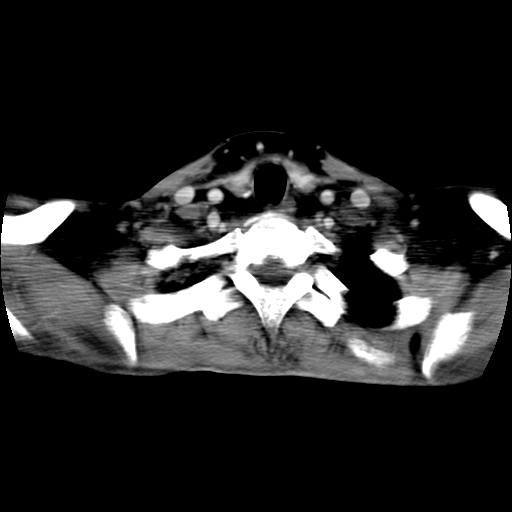

标题: CT24019:男,45岁,发现颈部肿物5个月。 [打印本页]

男,45岁,发现颈部肿物5个月,彩超示:双侧颈部及下颌部软组织增厚。

考虑双侧颈项部良性对称性脂肪增多症。